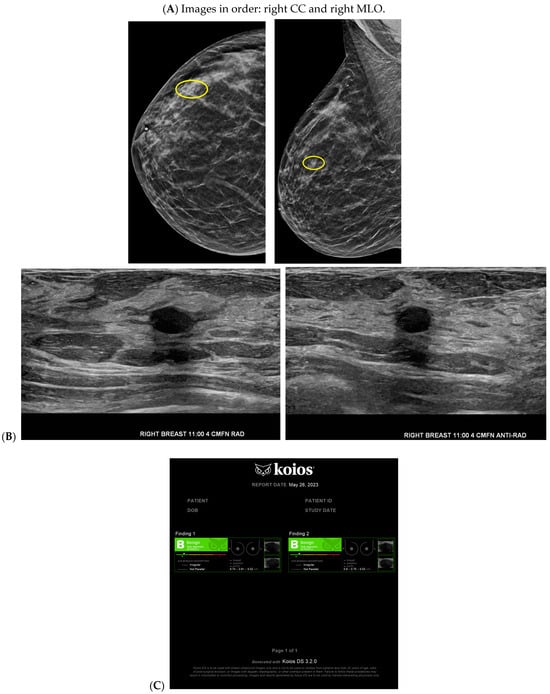

With the widespread implementation of DBT, which increases mammographic cancer detection sensitivity, there are larger volumes of images. This may ultimately increase the risk of reduced accuracy, perhaps due to reader fatigue and increased reading time [24]. There are numerous tomosynthesis AI products available, and at our institution we have implemented the use of Transpara, which is a deep learning-based AI system that uses deep CNN to help improve early-stage cancer detection and sensitivity (at similar specificity), while reducing reading time [24,25]. We view tomosynthesis AI as a valued asset to our clinical practice, as the software highlights potential areas of concern that require additional attention (Figure 1 and Figure 2). However, some areas flagged as concerning are often classically considered benign, such as stable post-lumpectomy sites, stable asymmetries and calcifications, or previously biopsied benign findings. That being said, tomosynthesis AI has been found to have a synergistic effect on cancer detection rate (CDR) when utilized by the radiologist. A study found that radiologist-only CDR was 67.3% and AI-only CDR was 72.7%, but when the radiologist and AI software were used together, the CDR increased to 83.6% [17,25,26]. Lunit INSIGHT MMG, Seoul, South Korea was the diagnostic support software used in this particular study [26].

Figure 1.

Developing asymmetry detected by artificial intelligence (AI): Between the baseline screening mammogram (A) and the follow-up screening mammogram 17 months later (B), there has been a very subtle development of left breast asymmetry that is difficult to perceive with the naked eye. However, the AI program Transpara highlighted potential regions of interest (C) for the radiologist to query for additional mammographic and sonographic imaging. On further diagnostic imaging, the subtle asymmetry corresponds to a hypoechoic mass at left 4:00, 3 cm FN (D) with hypervascularity (E). AI program Koios correctly recognized the mass as “Probably Malignant”, and this area returned as a biopsy-proven invasive malignancy with lymphangitic spread (F). Images obtained from the Icahn School of Medicine at Mount Sinai.

Cancer detection systems typically involve neural networks, machine learning, or deep learning developed from training models to recognize patterns, while diagnostic systems use an additional algorithm to classify [17]. Several CNN models have been developed to correlate ultrasound imaging features of a lesion with the four-classification breast cancer molecular subtypes [42]. Our institution uses Koios, which utilizes machine learning and AI to generate the probability of malignancy of a breast finding by evaluating a region of interest (ROI) selected by a radiologist [3,5]. Ultrasound AI has been found to reduce intra- and interobserver variability and to improve accurate BI-RADS classification of sonographic breast findings [3,5]. Ultrasound AI can also increase CDR [5] and reduce the number of unnecessary biopsies [5,43,44] (Figure 1, Figure 3, and Figure 4).